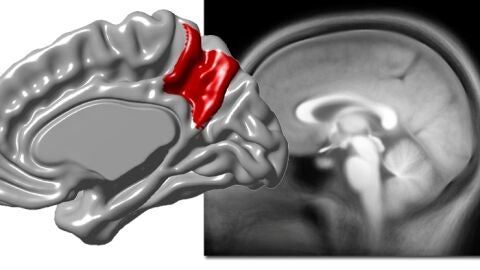

El paleoneurólogo Emiliano Bruner, investigador del Centro Nacional de Investigación del Centro Nacional de Investigación sobre la Evolución Humana (CENIEH) acaba de publicar en la revista Neuroscience, con la colaboración de la Universidad Autónoma de Madrid y de la Universidad Complutense de Madrid, un nuevo artículo sobre la neuroanatomía de las áreas parietales, en concreto sobre la superficie cortical del precúneo, cuyos resultados evidencian que su marcada variabilidad neuroanatómica entre los adultos se debe a un aumento de su volumen, y no solo a un cambio de sus proporciones.

En particular, se demuestra que las diferencias entre los individuos están asociadas a variaciones de la superficie de la corteza cerebral.